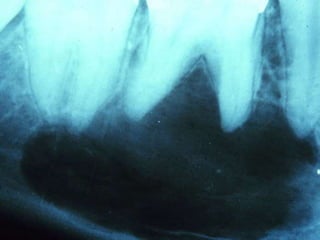

Condensing Osteitis

 4% to 8% of population

 Focal areas of radiodense sclerotic bone

 Mandible, apices of first molar

 Reactive bony sclerosis to pulp inflammation

 Irregular, radiopaque

 Stable, no treatment required

Condensing Osteitis  4%to 8% of population  Focal areas of radiodense sclerotic bone  Mandible, apices of first molar  Reactive bony sclerosis to pulp inflammation  Irregular, radiopaque  Stable, no treatment required